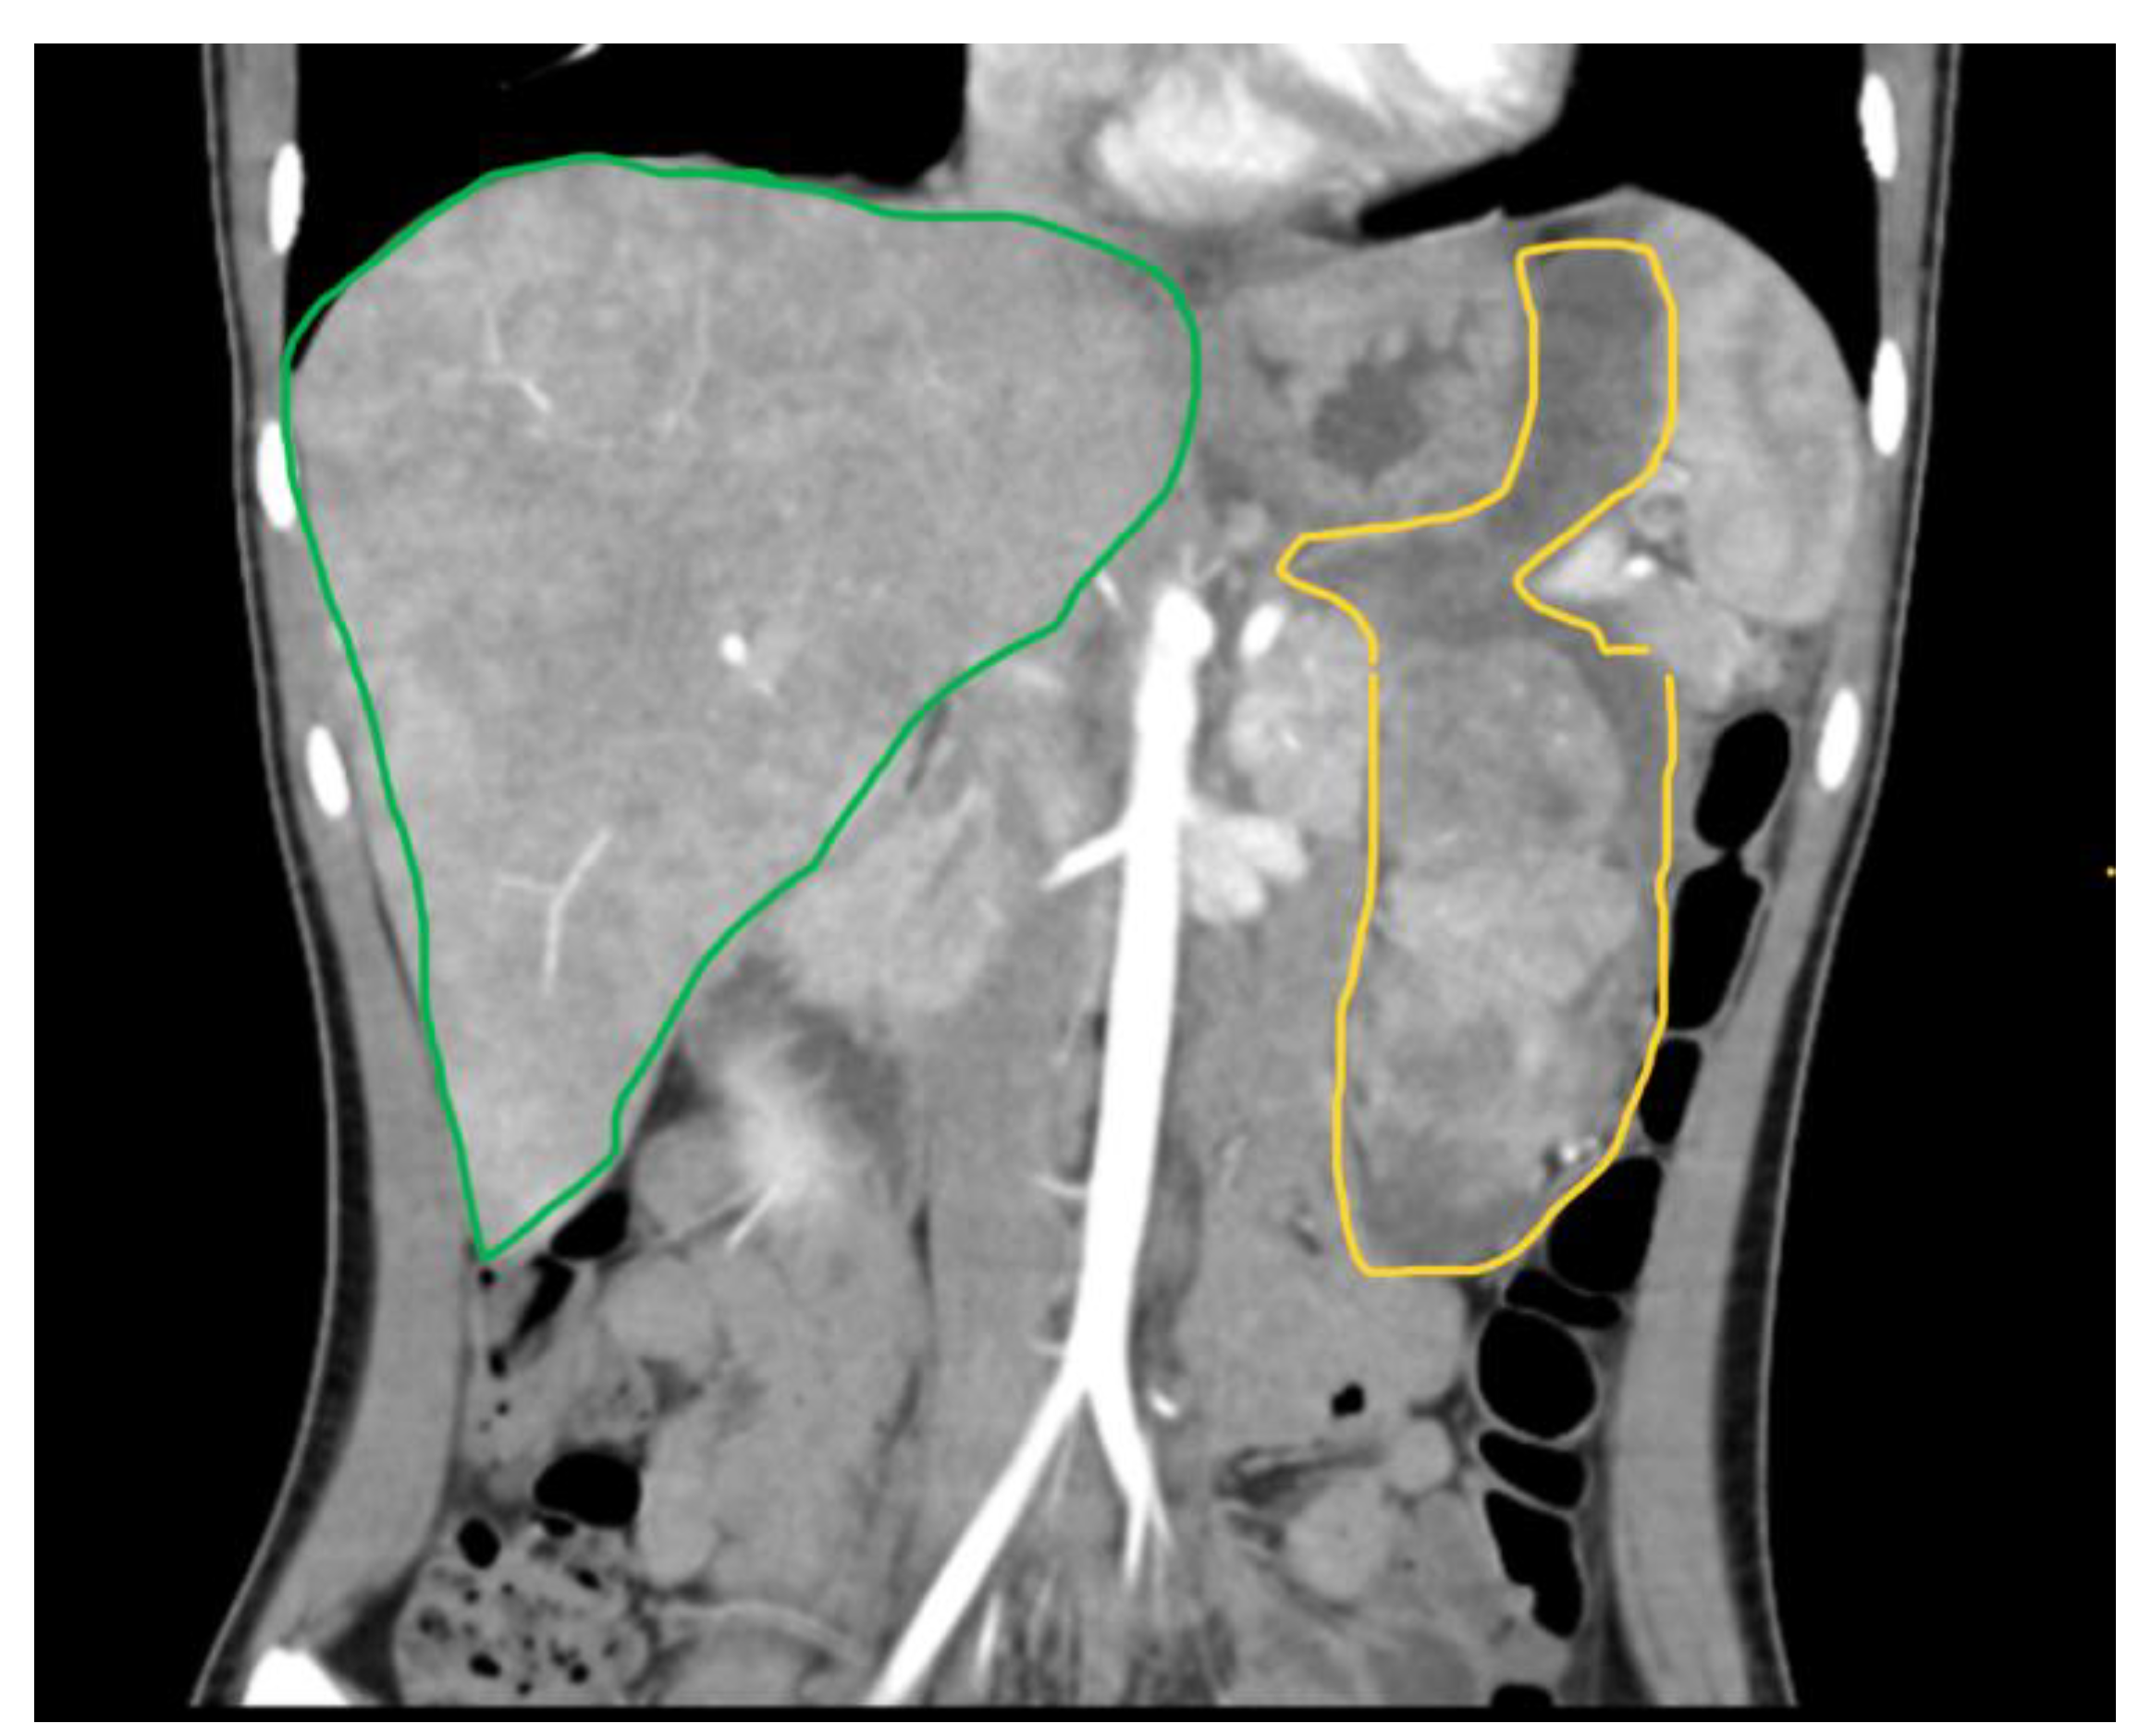

8. Case Report

Case Discussion